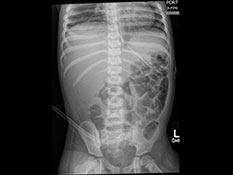

X-ray - An x-ray takes a picture of the bones inside your child’s body. Each picture takes just a couple of seconds, like a regular photograph.